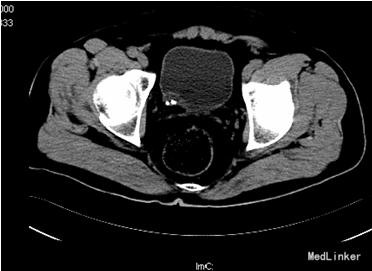

患者,男,55岁8月,因“反复腰背部胀痛6+月”入院。6+月前,患者无明显诱因出现腰背部间歇性胀痛,无发热、恶心、呕吐,无尿频、尿急、尿痛,无肉眼血尿等症状,于当地医院查彩超示“双肾结石”行“左肾结石体外震波碎石”,因“右肾囊肿”而未处理“右肾结石”,术后患者恢复良好,无发热、腹胀、腹痛等不适。此后患者反复出现右侧腰背部不适,未予特殊处理。10+天前,患者自觉右侧腰背部胀痛加重,呈持续性,不伴发热,无肉眼血尿,无尿频、尿急、尿痛等症状,遂于我院门诊行CT示“右肾柱形状结石,右肾积水,右肾萎缩,右侧输尿管下段膀胱入口处结石影”。现患者为进一步诊治入院。

查体:腹部外形正常,全腹柔软,无压痛及反跳痛,腹部未触及包块,肾脏未触及;右肾区叩痛明显,左肾区无叩痛;双侧输尿管压痛点无压痛。 CT:右肾柱形状结石,右肾积水,右肾萎缩,右侧输尿管下段膀胱入口处结石影; 核素肾显像:左肾GFR:30.2ml/min,右肾19.4ml/min。

诊断:1、右肾结石 2、右侧输尿管开口囊肿 3、右侧输尿管下段结石 4、右肾囊肿 5、尿路感染 行右肾碎石术,术中见:右侧输尿管开口处一囊肿,约1.0cm×0.8cm,压迫右侧输尿管开口,随输尿管口喷尿时呈隆起行改变,囊肿内发现一大小约0.5×0.2cm大小结石,右肾盂大量沙粒样结石。